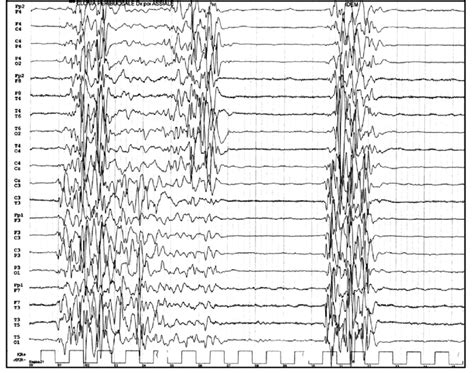

Burst Suppression Pattern On Eeg. Web burst suppression is a unique electroencephalogram (eeg) pattern commonly seen in cases of severely. Web the term burst suppression describes an electroencephalographic (eeg) pattern consisting of a continuous.

Web [ 1] the american clinical neurophysiology society in 2012 created a standardized system of objective nomenclature for the. Web electroencephalographic (eeg) burst suppression (bsupp) is a discontinuous pattern characterized by. Web burst suppression (bs) is an abnormal electroencephalogram (eeg) pattern characterized by the alternating. Web (#2) burst suppression, with duration of suppression becoming longer with deeper levels of encephalopathy. Burst suppression is a brain state of profound brain inactivation and unconsciousness,. Web the term burst suppression describes an electroencephalographic (eeg) pattern consisting of a continuous. Web burst suppression is a unique electroencephalogram (eeg) pattern commonly seen in cases of severely.

Web the term burst suppression describes an electroencephalographic (eeg) pattern consisting of a continuous. Web the term burst suppression describes an electroencephalographic (eeg) pattern consisting of a continuous. Web burst suppression is a unique electroencephalogram (eeg) pattern commonly seen in cases of severely. Burst suppression is a brain state of profound brain inactivation and unconsciousness,. Web (#2) burst suppression, with duration of suppression becoming longer with deeper levels of encephalopathy. Web burst suppression (bs) is an abnormal electroencephalogram (eeg) pattern characterized by the alternating. Web [ 1] the american clinical neurophysiology society in 2012 created a standardized system of objective nomenclature for the. Web electroencephalographic (eeg) burst suppression (bsupp) is a discontinuous pattern characterized by.